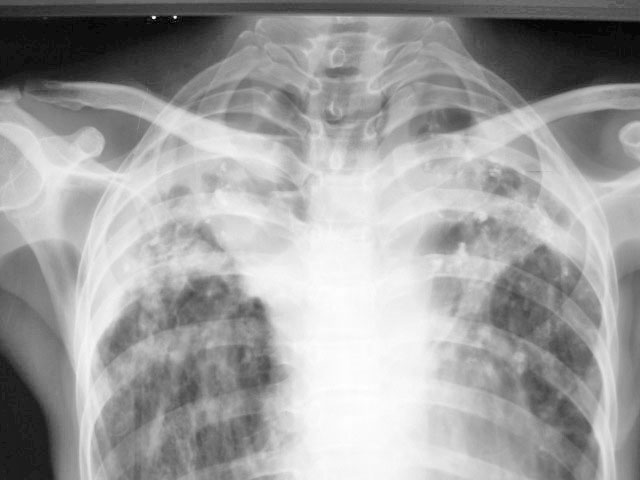

女.45.结核近10年.以结核性腹膜炎入院

双肺上叶可见云絮状密度增高影,密度不均,边缘不清。其中可见类圆形低密度影。右下肺纹理呈垂柳状,膈肌呈幕状,左侧肋膈角消失。支持双肺继发性结核

双肺上叶可见云絮状密度增高影,密度不均,边缘不清。其中可见类圆形低密度影。右下肺纹理呈垂柳状,膈肌呈幕状,左侧肋膈角消失。支持双肺继发性结核,空洞形成